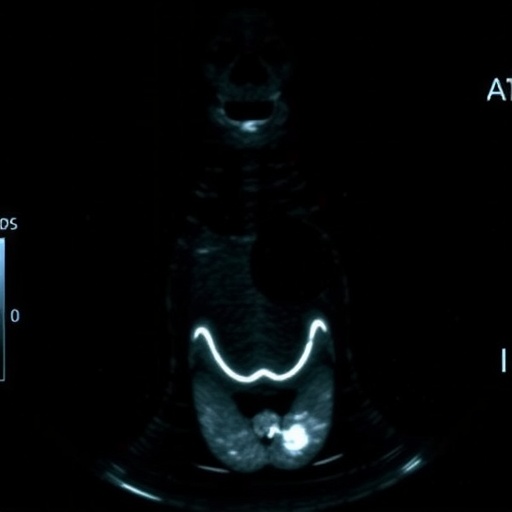

To distill the most predictive features from the imaging data, the researchers employed the Least Absolute Shrinkage and Selection Operator (LASSO) logistic regression method. This approach identified five key variables strongly associated with HVCLNM: tumor size, multifocality, enhancement direction observed in CEUS, peak intensity of contrast uptake, and lymph node status as reported by ultrasound. These factors were then integrated into a statistically rigorous nomogram, which provides individualized risk assessments based on patient-specific imaging profiles.

The integration of contrast-enhanced ultrasound represents a notable advance in thyroid cancer imaging. Unlike traditional ultrasound techniques that provide anatomic detail, CEUS captures dynamic vascular features—information that is particularly relevant given the angiogenic nature of metastatic lymph nodes. By incorporating enhancement patterns and flow directionality, the nomogram leverages subtle imaging biomarkers that correlate strongly with metastatic burden.